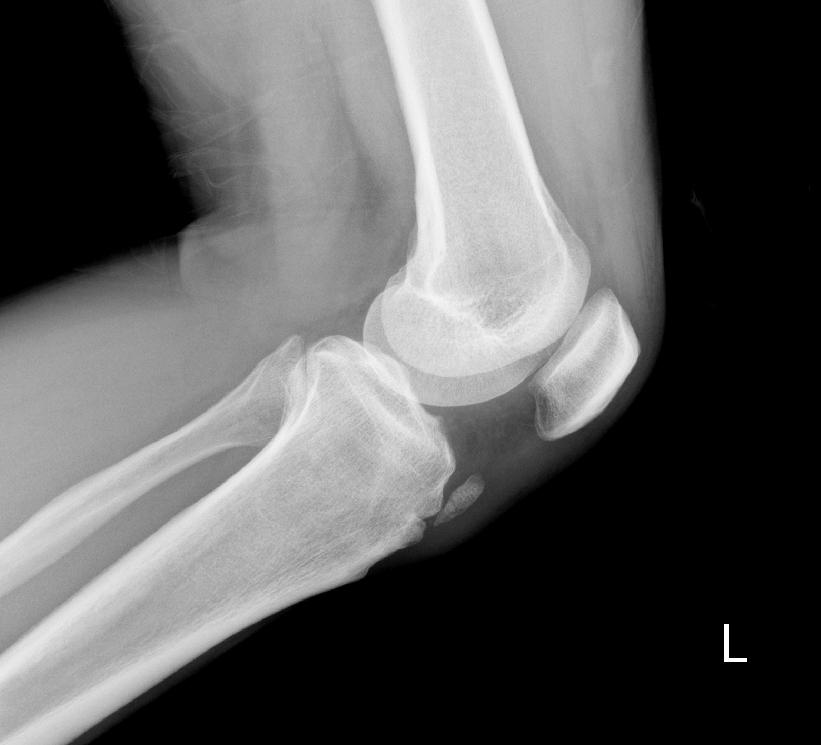

标题: X2880:胫骨结节前方的小骨是什么?

会不会是副髌骨???其内似可见骨小梁,如果是钙化可能不会有骨小梁吧??疑问中……

胫骨结节骨软骨炎

没融合的骨骺.或膑韧带钙化.

应该是副骨

是多个骨化中心在发育过程中没有合并所导致

完全可以排除髌韧带钙化.考虑发育原因或以前有过胫骨结节骨软骨炎病史.

考虑发育原因或以前有过胫骨结节骨软骨炎病史.

髌韧带钙化,考虑以前患过胫骨结节骨软骨炎

软组织骨化,髌韧带骨化可能性大。

应该是胫骨结节骨软骨病 可以双侧对比

没融合的骨骺

二次骨化中心未融合.~